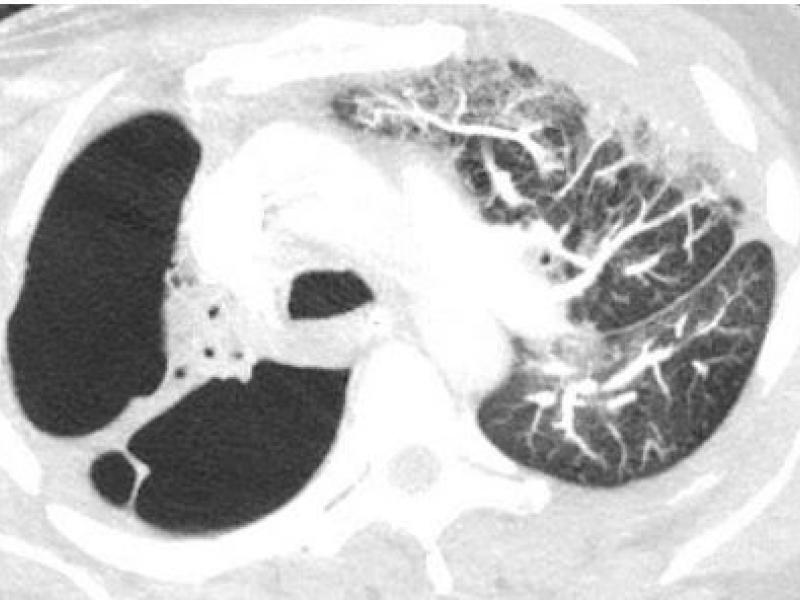

What's the Diagnosis? By Dr. Abby Renko

September 01 2021

A 60 yo F presents to the ED w cough and dyspnea. History is